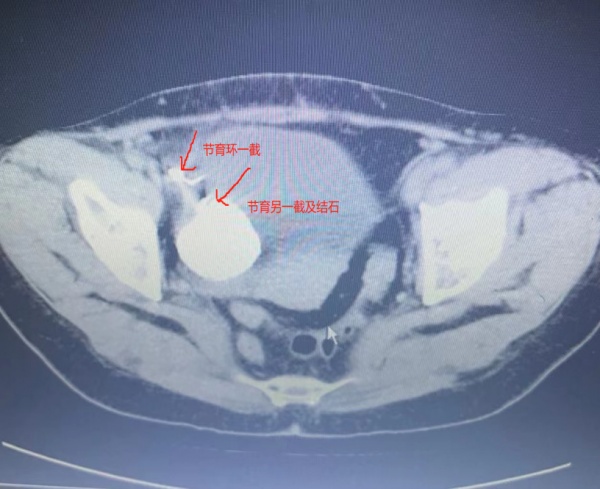

患者CT影像。

“普通的节育环移位不会伴随尿频尿痛症状多年,陈女士身上可能还存在其他没有发现的问题。”入院后,妇科主任刘海琳及副主任熊志芳第一时间安排陈女士做了腹部盆腔CT检查。检查结果提示:节育环的一端位于膀胱外,另一端位于膀胱内。棘手的是,膀胱内还存在4厘米的大结石与节育环融合。

鉴于陈女士的特殊情况,妇科请来了泌尿外科专家潘炜主任会诊。潘炜结合患者CT片检查结果,与熊志芳及麻醉科甘亚倩副主任协同制定了完备的手术及麻醉方案。